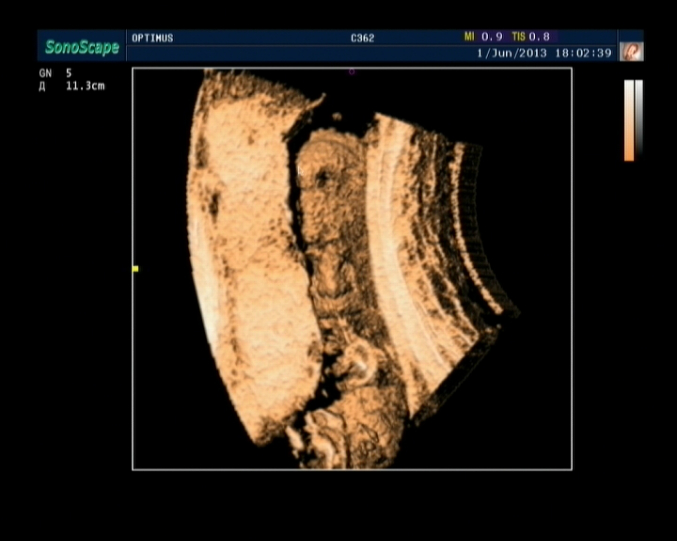

Результаты: УЗИ, КТГ, доплера, скринингаНу вот,наконец-то сходили мы на 3D УЗИ.Всё очень понравилось,делали почти час,всё рассказывали,показывали,малыш наш очень активный,постоянно барахтался,пяточку трогал,с пуповиной играл,видели как зевает,2 раза,так классно=))) Папе тоже очень понравилось=) Фото долго не получалось,да и не получилось как надо,малыш прятался=( И так,момент истины,у нас будет

Ну и вот наш сынок=))) Не знаю,разглядите или нет=)